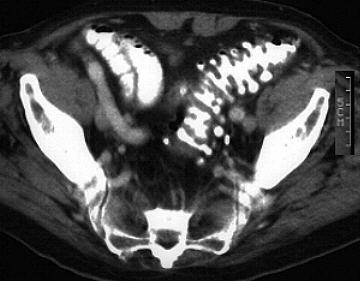

Das kolorektale Karzinom befällt bevorzugt Sigma und Rektum und entsteht häufig durch Entartung von Polypen. Wichtig für die CT-Diagnostik ist eine gute Kontrastmittel- oder Wasserfüllung des Kolons. In frühen Tumorstadien kann eine verdickte Darmwand dargestellt werden. In weiter fortgeschrittenen Tumorstadien stellt sich eine kontrastmittelaufnehmende weichteildichte Raumforderung dar, die das Darmlumen einengen kann. Mangelnde Abgrenzbarkeit des perirektalen Fettgewebes sowie streifige Ausläufer sprechen für ein organüberschreitendes Tumorwachstum. Häufig finden sich kontrastmittelaufnehmende Lymphknotenmetastasen im perirektalen Fett.

Carcinoma of the sigmoid colon (Sigmakarzinom)

Rectal carcinoma with perirectal metastases